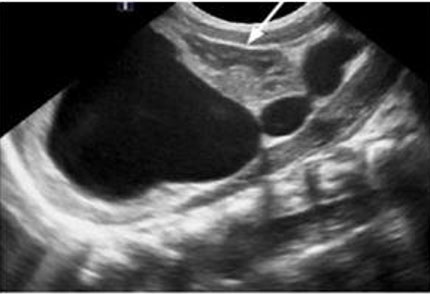

The fetal urinary tract has a very intricate development process and is the most common system affected by congenital defects [1]. Congenital anomalies of the kidneys and the urinary tract (CAKUT) account for approximately 30% of all congenital malformations. Abnormalities can affect the upper urinary tract such as the kidneys and the ureters and the lower urinary tract, impacting the bladder and the urethra which will then affect the amniotic fluid volume. Congenital anomalies of the kidneys and the urinary tract causes include genetic etiologies, maternal diet, and fetal exposures [2]. The antenatal detection of the anomalies, which is at 73.87%, has helped improve outcomes [3]. The most used imaging tool is ultrasound, furthermore it is standard practice to visualize the kidneys and the bladder during the second trimester ultrasound in pregnancy (Figure 1A and Figure 1B) [4]. The spectrum of outcomes for these patients ranges from no clinical significance to more serious outcomes such as pulmonary hypoplasia and end-stage renal disease [1],[5]. While each malformation has a different male to female ratio, CAKUT impacts more males [3]. A multidisciplinary care team is important when diagnosing, managing, and treating CAKUT. In this review, we will discuss the relevant embryological process and discuss different anomalies (Figure 1A and Figure 1B).

Figure 1: Normal ultrasound views of the kidneys. (A) Coronal views in a 12-week fetus, (B) axial view of the kidneys at 20 weeks and 6 days [26]. Radiological images were obtained from open-access article distributed under the terms of the Creative Commons Attribution License (CC BY) [26].